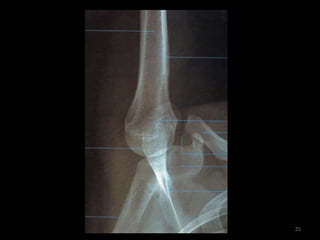

Incidência AP de cotovelo62

63

64